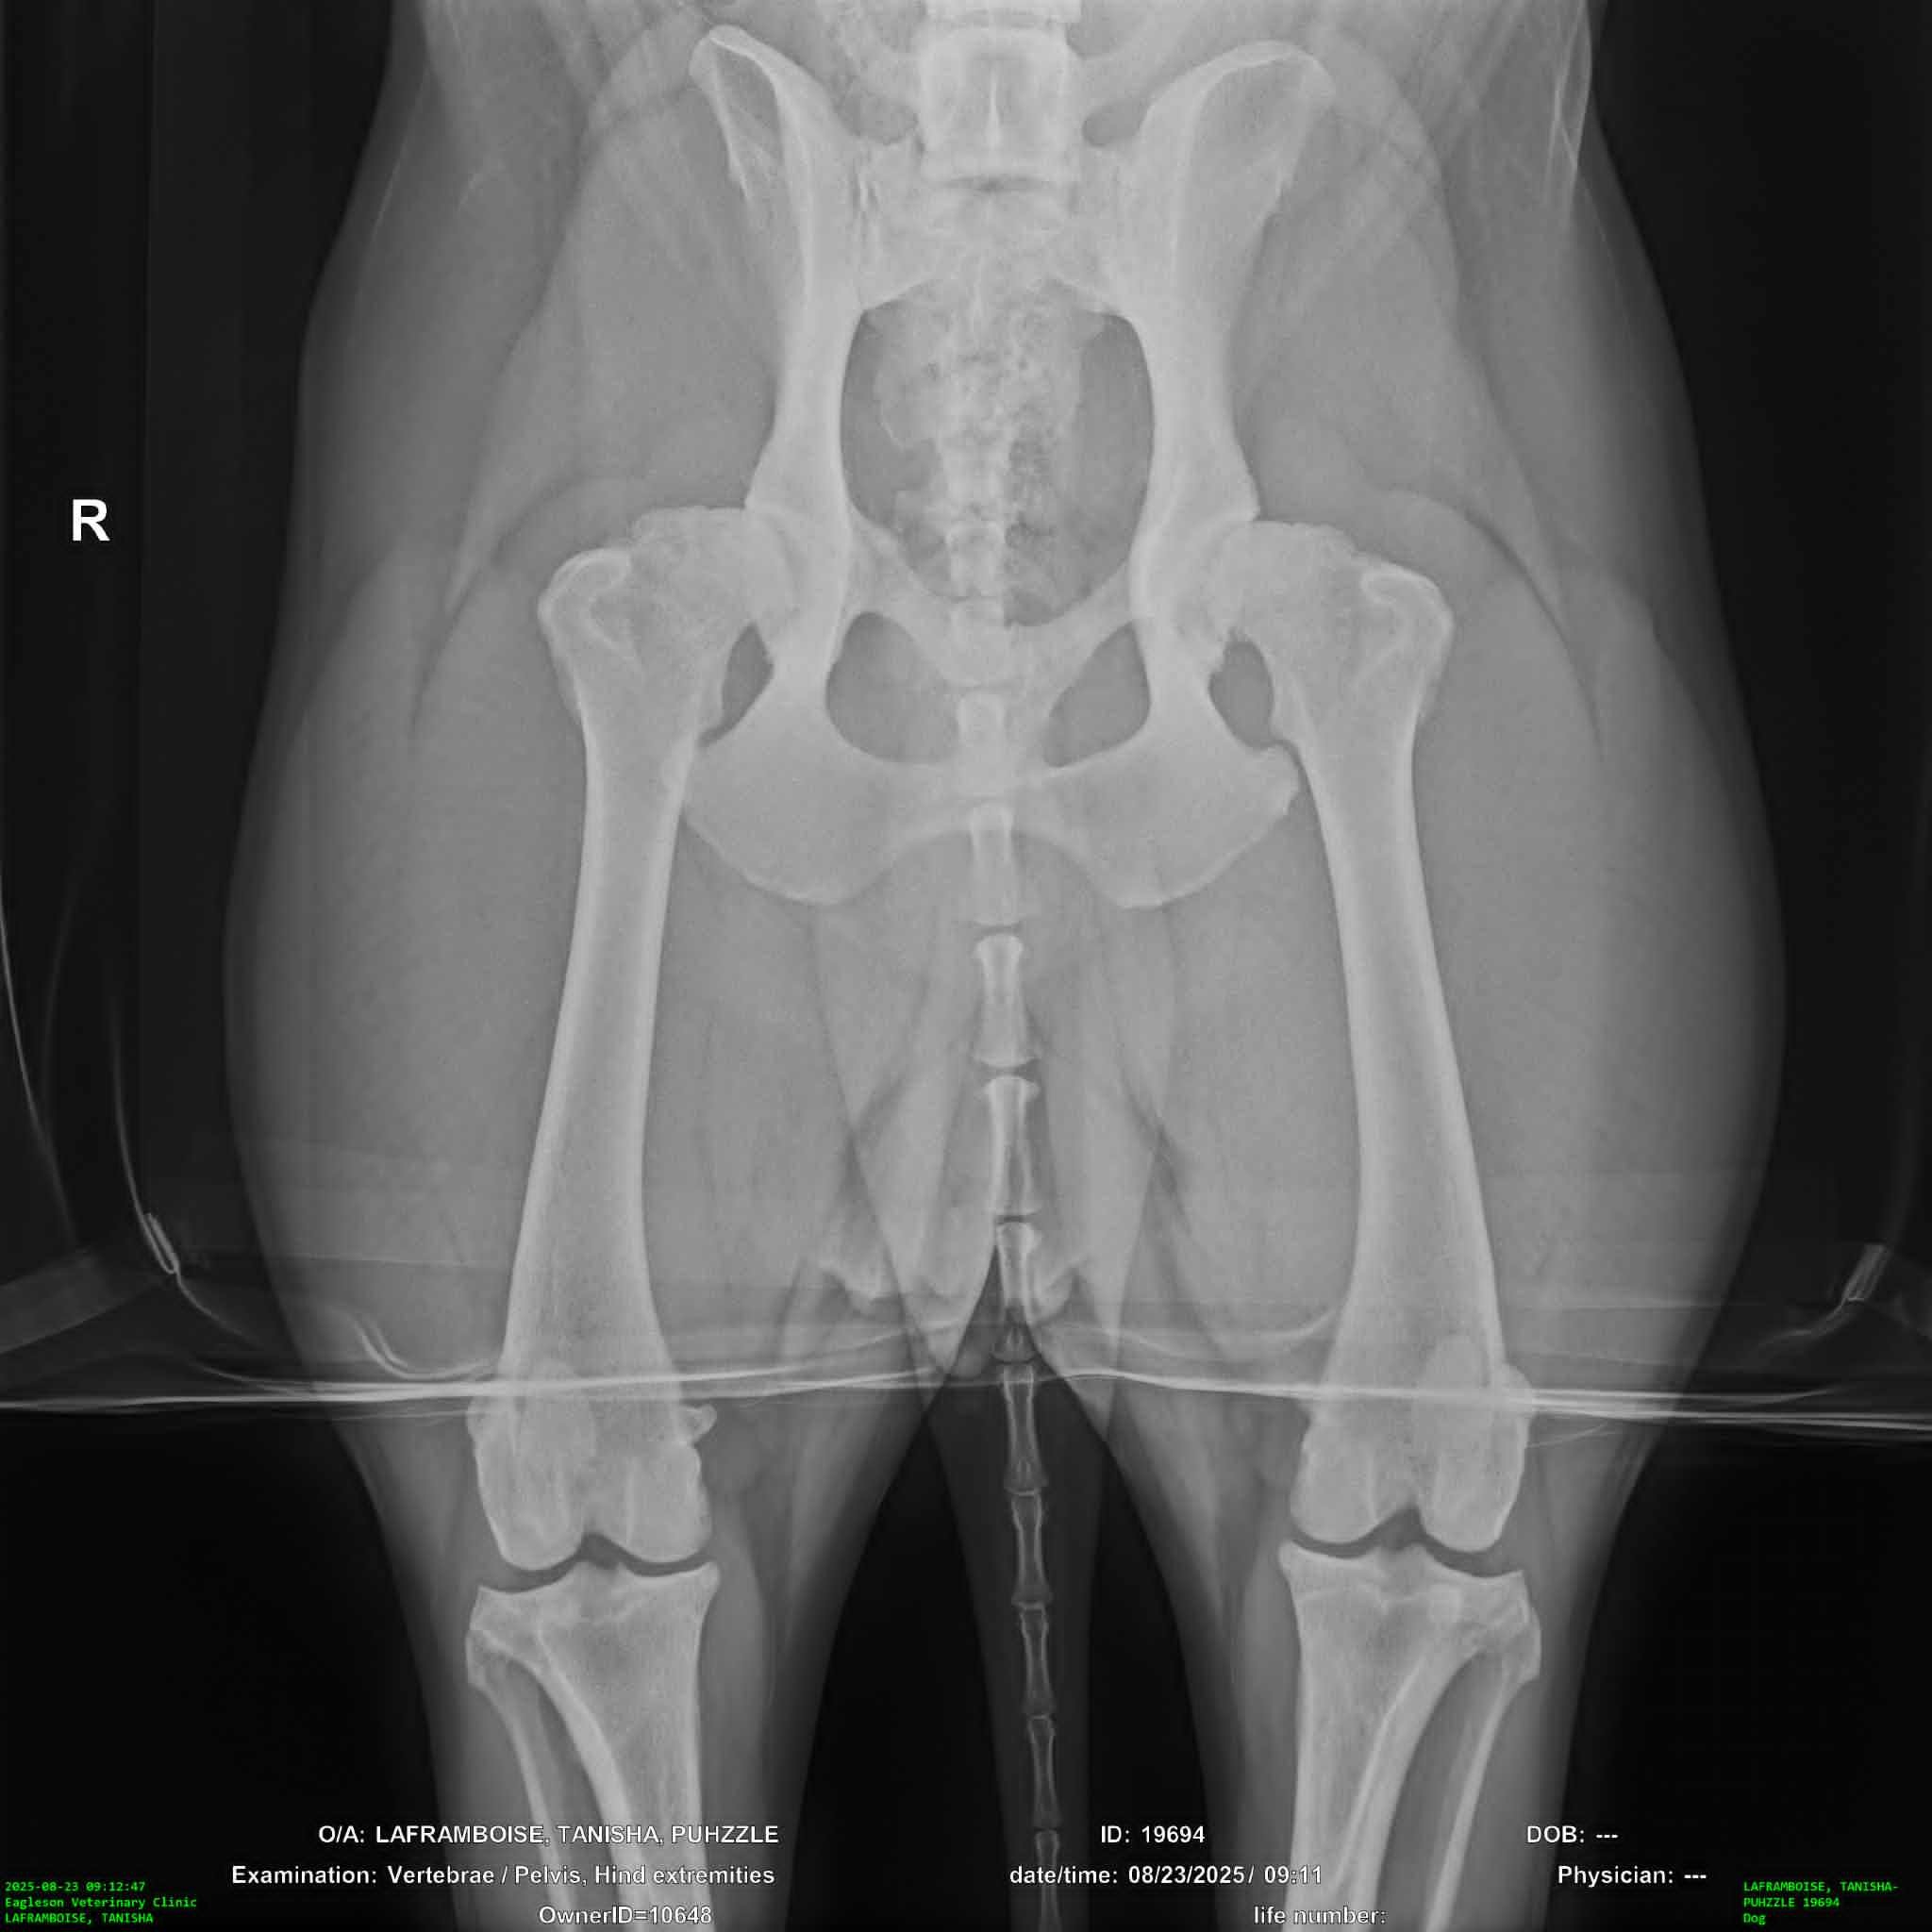

Hello my name is Zach and my wife Tanisha and I are desperately trying anything we can to raise the funds for our dog-ters TPLO surgery. After we had arrived home in the evening my wife noticed she was limping on her walk. We crate rested her for the night and woke up early to see if she would still be limping in the morning. When she was we immediately took her to emergency at our regular vet who did x-rays and actually diagnosed Puhzzle with Bi-lateral hip dysplasia and told us she would need hip surgery. We started some pain management and got a referal to an Orthopedic vet near us to start discussing options. During our consultation with our surgeon he mentioned feeling a little concerned about one of her x-rays and the consultation quickly turned into an exam. He explained to us that yes Puhzzle has Bi-lateral hip dysplasia, but as she's 4 and has had no issues running, jumping, or being a dog that he suspected her hips aren't her current issue. He did an exam on her legs and found she has a partially torn ACL that will require surgery to fix, luckily he mentioned that once they get the TPLO surgery they do not need another on that particular knee and she'll gain 98-99% functionality but the other ACL is high risk for injury within 6-12 months because this injury is genetic, being a structural flaw of how her liagaments rub on the bone while moving. My wife and I are saving everything we can and have her surgery currently scheduled for November 20th, because she needs the surgery sooner than later, to avoid further injuring herself, and any donation towards her surgery would mean so much to us.